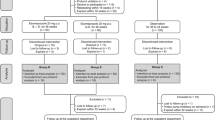

Method: The model adopted a 30-day time horizon and the perspective of third-party payers in the USA and Europe. The main efficacy variable was the number of averted rebleedings. Healthcare resource utilization costs (physician fees, hospitalizations, surgeries, pharmacotherapies) relevant for the management of PUB were also determined. Data for unit costs (prices) were primarily taken from official governmental sources, and data for other model assumptions were retrieved from the original clinical trial and the literature.

After successful endoscopic haemostasis, patients received either highdose IV esomeprazole (80mg infusion over 30 min, then 8mg/hour for 71.5 hours) or no-IV esomeprazole treatment, with both groups receiving oral esomeprazole 40mg once daily from days 4 to 30.